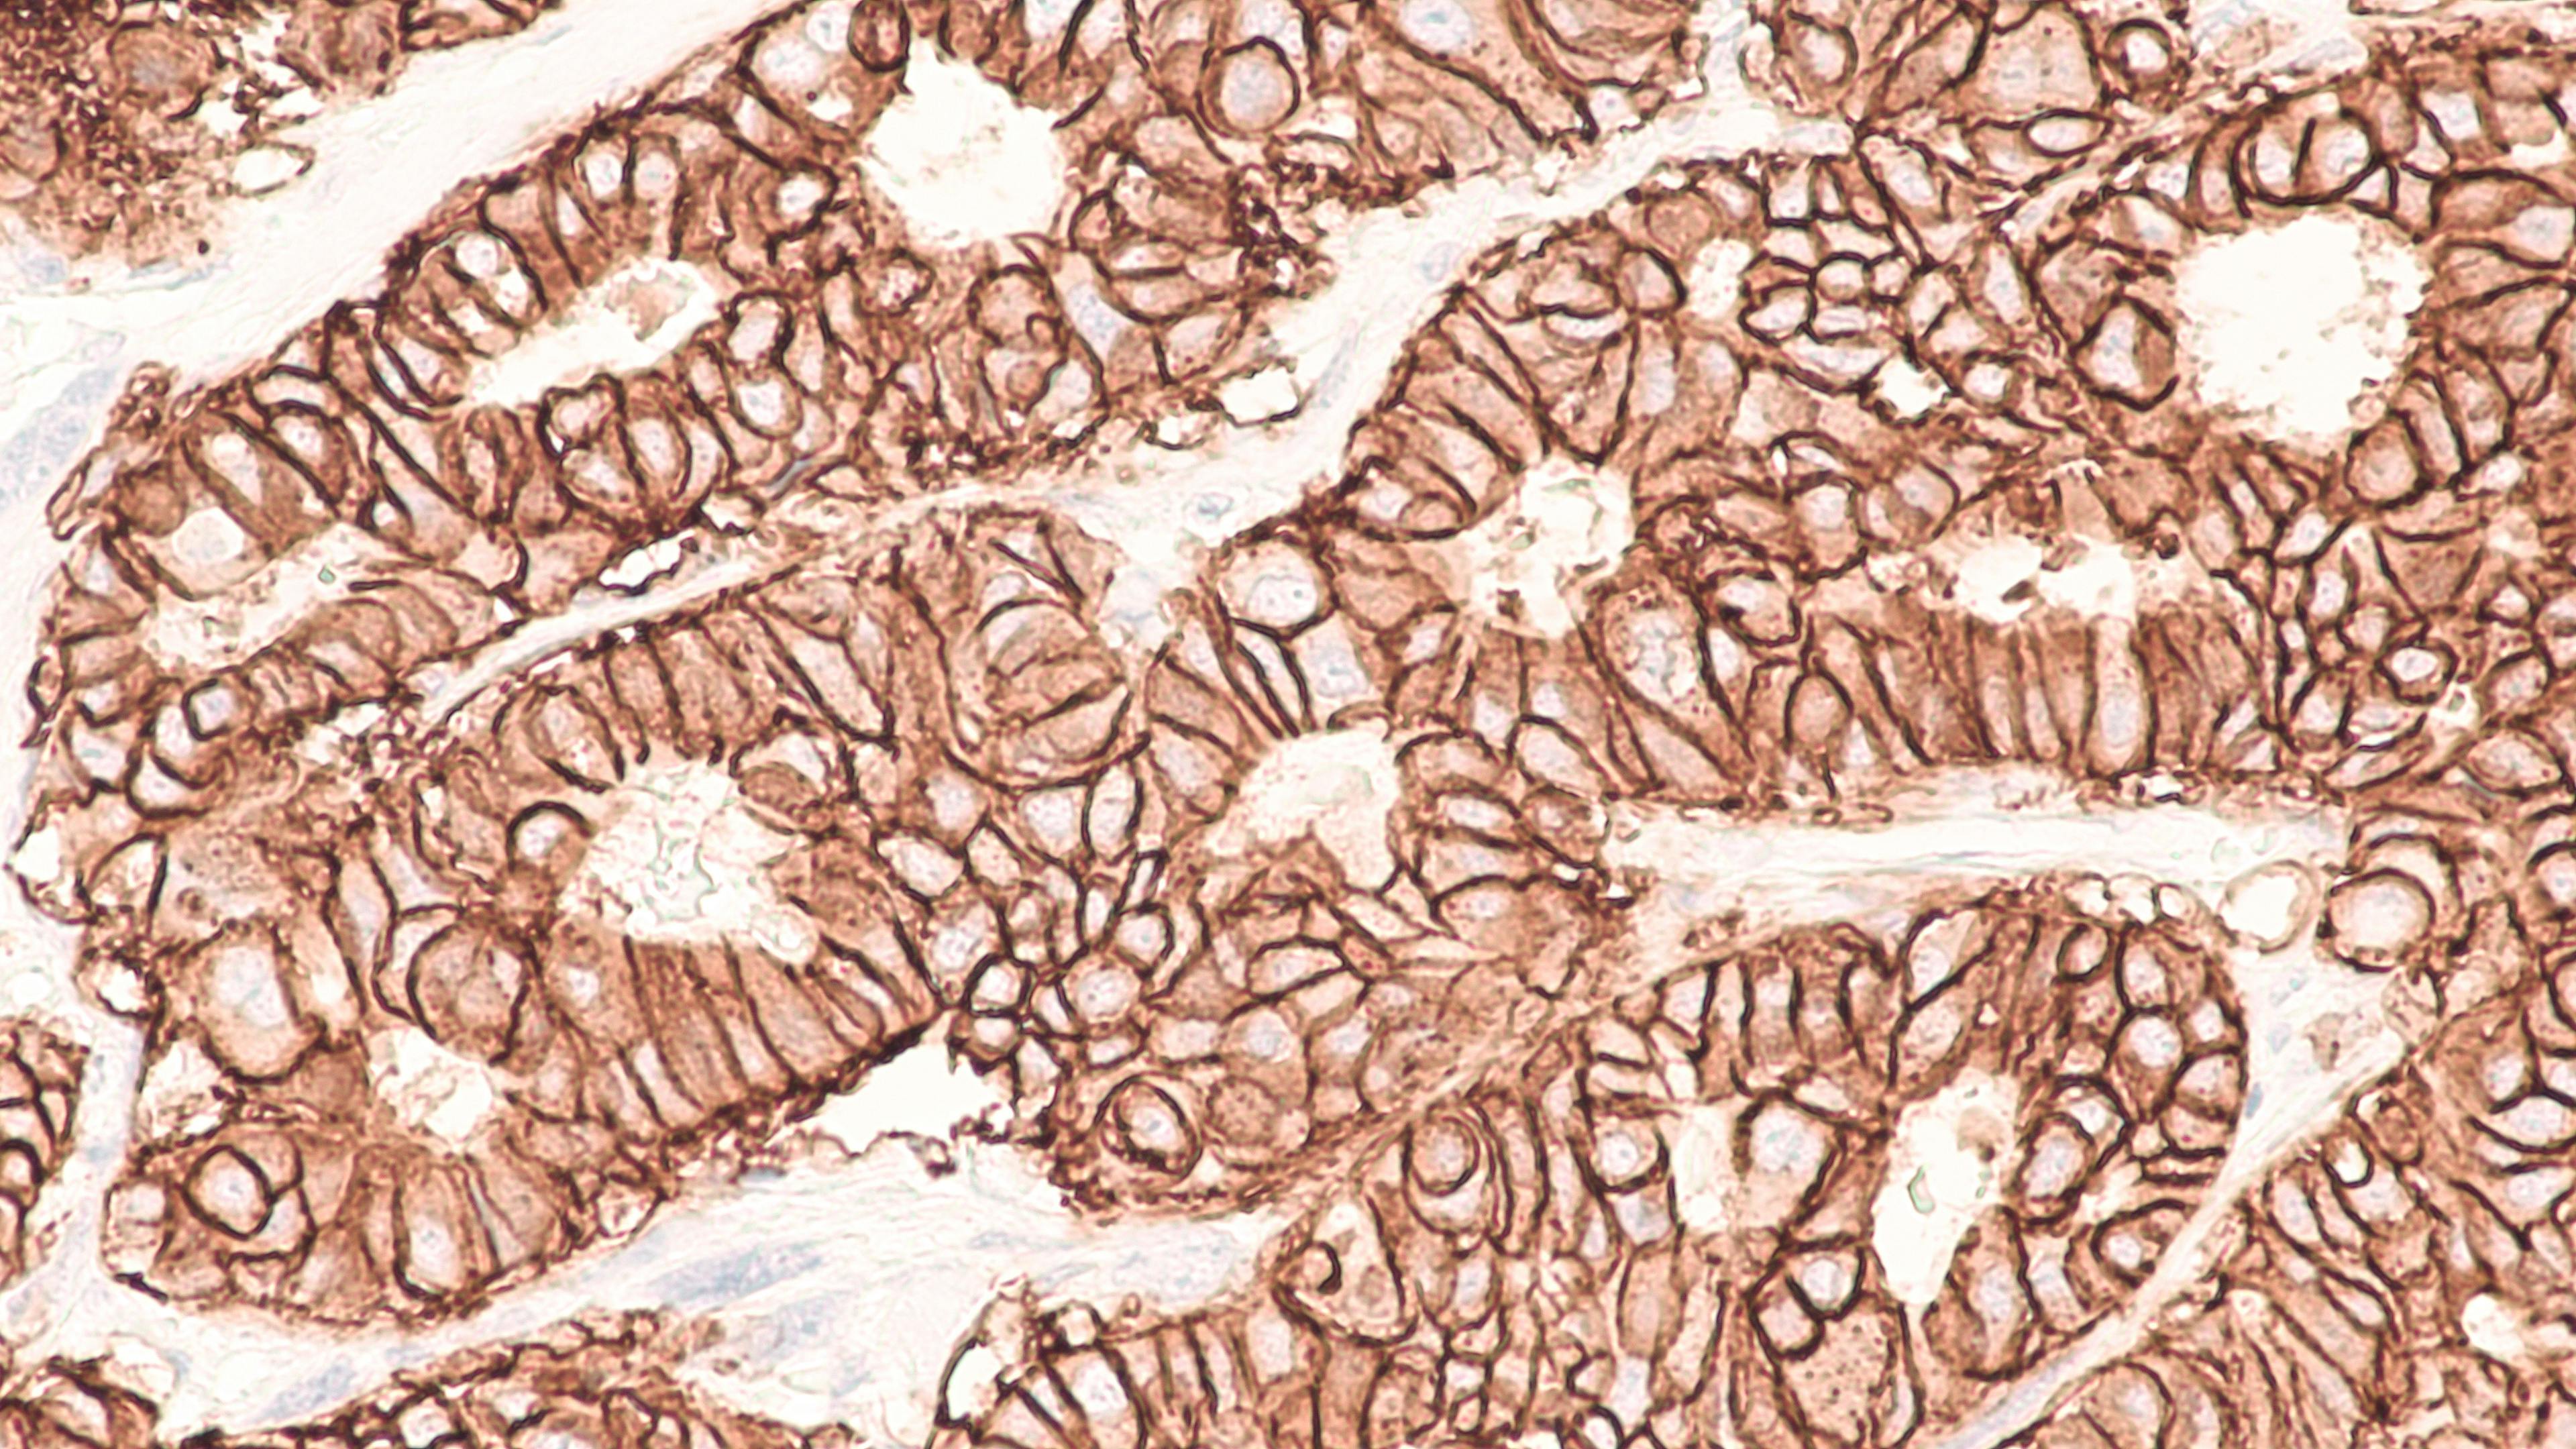

Pathology

Courtesy of Grundium

Virtual pathology streamlines rapid on-site evaluation (ROSE) and frozen sections for major multi-site academic hospital

How Grundium’s compact scanners improve efficiency and access in pathology.